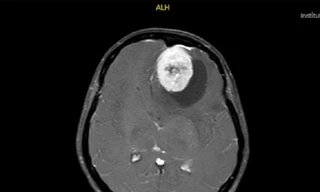

Thạc sĩ, bác sĩ Thân Văn Thịnh, Khoa Khám bệnh - Bệnh viện Ung bướu Hà Nội, cũng cho hay nhiều bệnh nhân ung thư phổi có biểu hiện đau đầu do bệnh đã di căn não, hoặc đau xương sống, sườn do di căn xương. Khi phát hiện các bệnh lý trên, đi khám, người bệnh mới phát hiện ung thư.